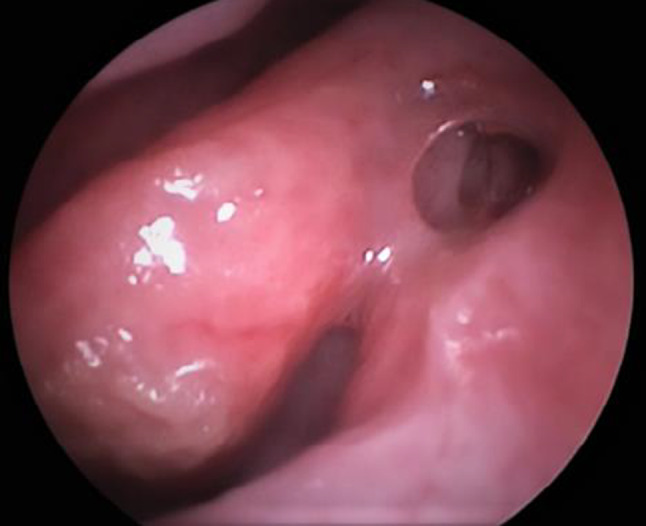

•Presence of a patent stoma as confirmed by nasal endoscopy (Fig. 4).

Fig. 4.

Post operative Rhinostomy opening (left side)